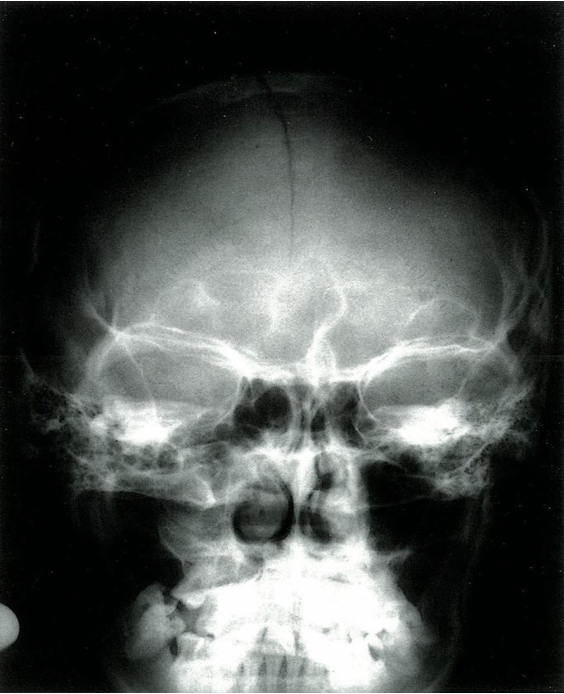

X-ray skull (PA view) A cranial vault fracture is seen as a linear lucency paralleling the sagittal suture